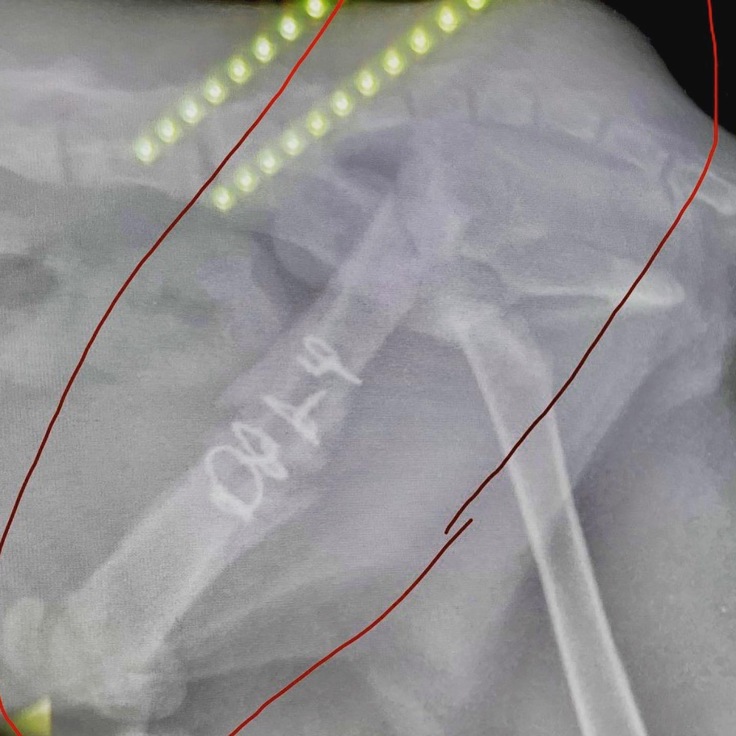

⑤再手術(9月16日)

ピンが皮膚を突き破りそうなため、摘出を行いました。幸い抜き取る事が出来たので、切開も小さい範囲で済みました。ワイヤーは残したままです。

皮膚はまだ盛り上がっていて、蓮も気になるみたいで舐めたり噛んだりしています。

骨はまだ散らばっていますので、左後脚に力を入れるのが難しく、走ったり飛んだり跳ねたりは出来ず、まだぎこちない歩き方です。

↓[摘出したピン]